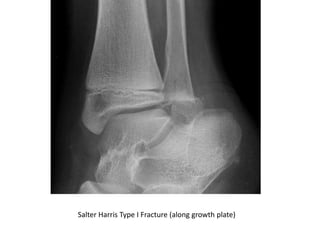

Salter Harris Type I Fracture (along growth plate)

Salter Harris TypeI Fracture (along growth plate)